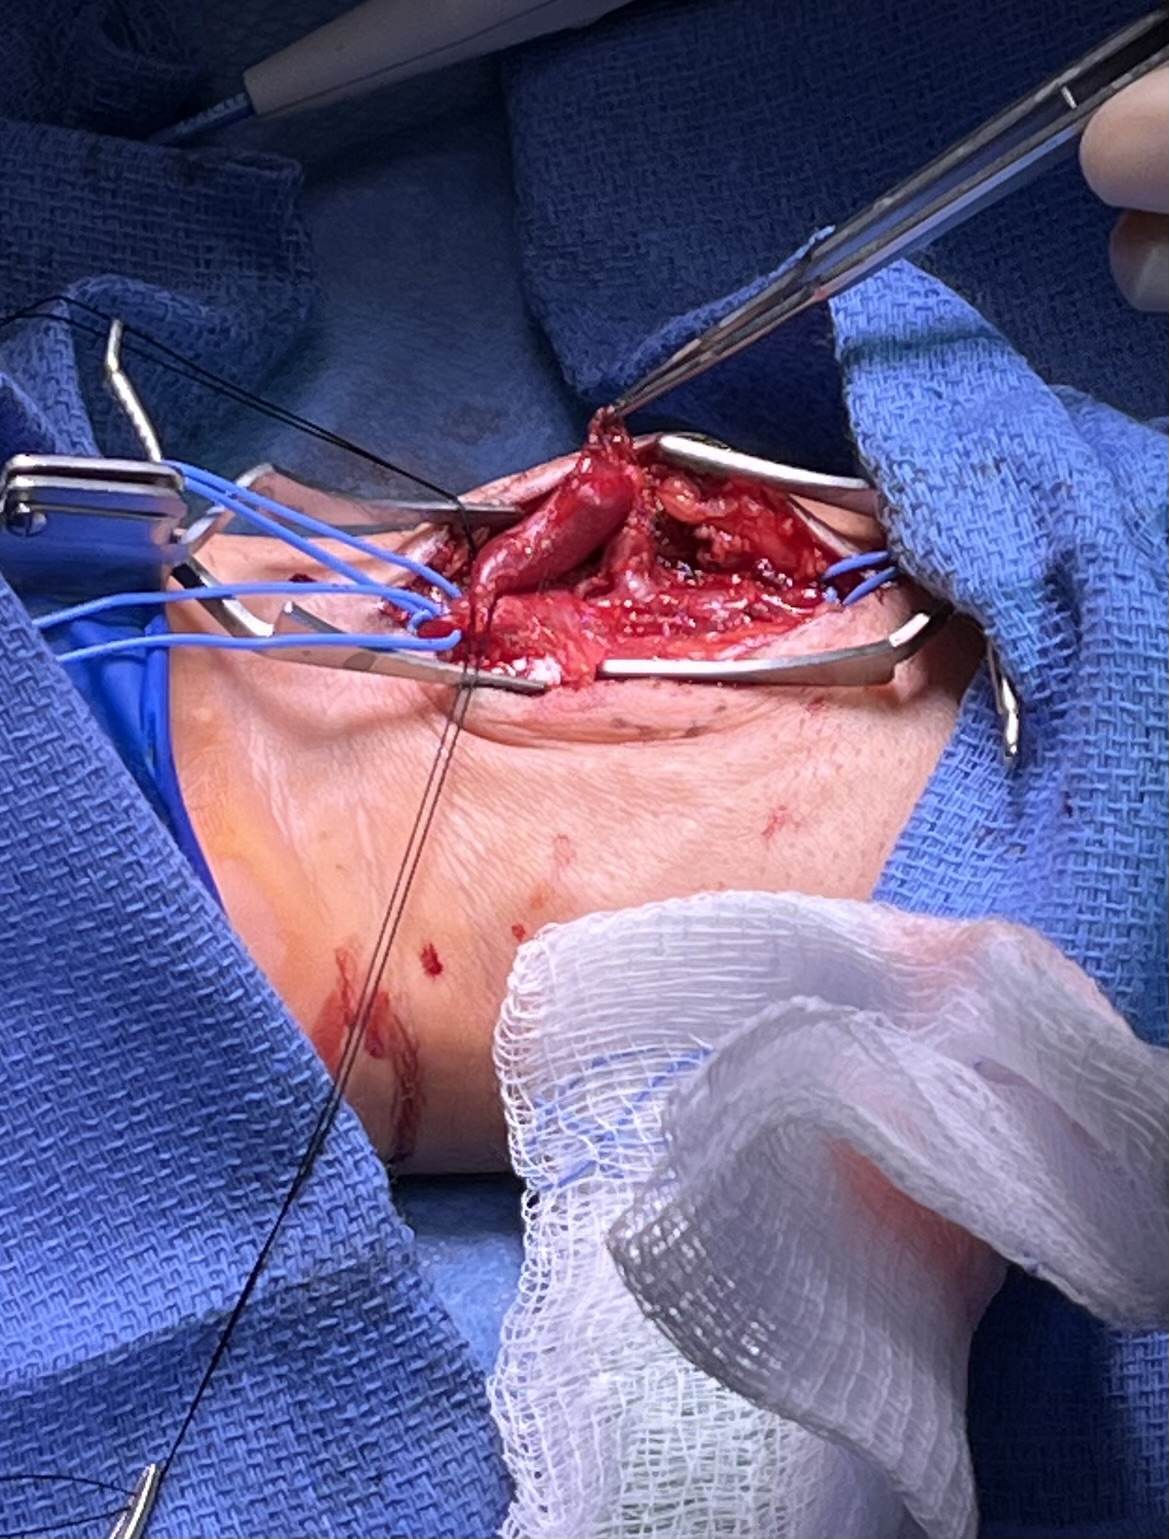

Due to the symptomatic nature and persistent AVF, the decision was made to pursue open repair with AVF ligation. Direct exposure of the distal radial artery was performed and the aneurysmal sac was isolated (Figure 3). The arterial inflow and venous outflow collaterals were ligated. The aneurysmal sac was then resected and sent for histologic examination, which revealed benign vessel and connective tissue. The radial artery remained intact and distal flow demonstrated with doppler post-ligation of arteriovenous fistula. The patient was discharged from the post anesthesia care unit after the procedure. Postoperative follow up was without any complications.